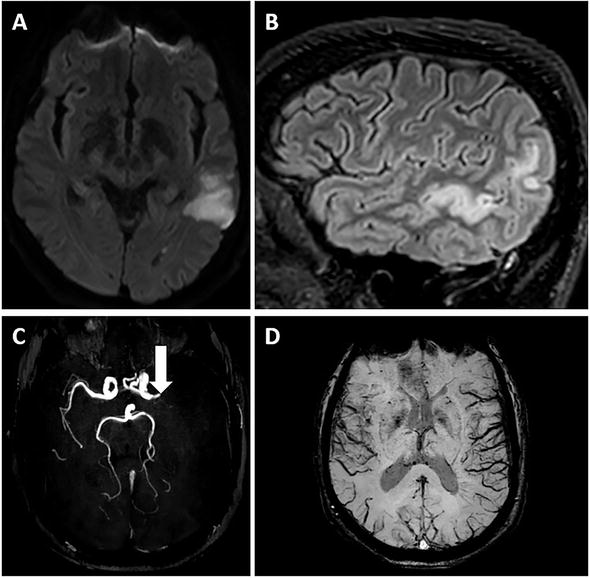

Brain MRI of a 54yearold man with transient global aphasia. A, B.... Download Scientific Diagram Sensory Aphasia Mri Transcortical aphasias include motor, sensory and mixed transcortical aphasia. A right temporal lobectomy revealed a glioblastoma. Parallel work using functional magnetic resonance imaging (fmri) has pinpointed a region in the posterior most portion of the left planum. Transcortical sensory aphasia is a language disorder characterized by fluent speech with paraphasic errors, severe comprehension difficulties, intact. Transcortical sensory aphasia (tsa) is. Sensory Aphasia Mri.